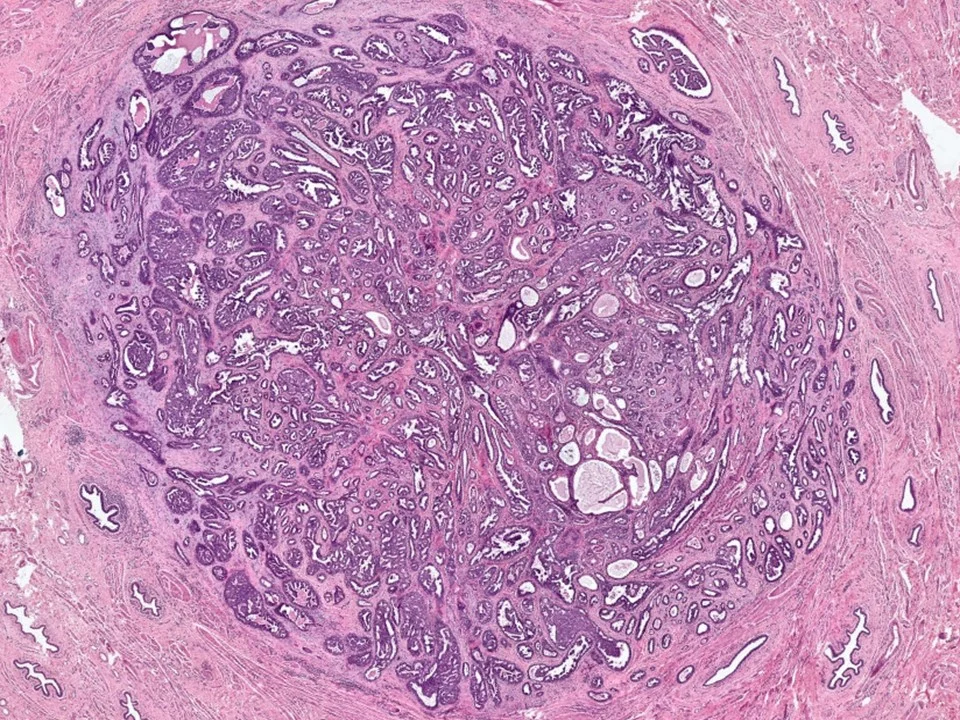

Nipple Adenoma